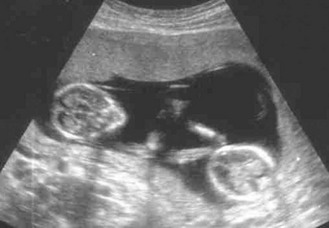

Normal findings: Abdominal organs are displaced during pregnancy so swelling may be difficult to identify, e.g. ovarian cyst, and pain and tenderness may not be in usual sites. The kidneys and liver cannot be palpated and listening for bowel sounds may be difficult in late pregnancy. In tall or thin patients, the SFH may be less than expected; in obese patients, it may be larger. Ultrasound scanning is now routinely used to assess fetal development (Figs 10.42 and 10.43).